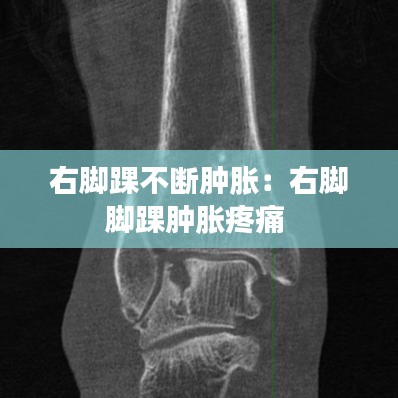

影像學檢查:如X光、MRI或超聲檢查,以排除骨折、關節(jié)損傷或其他結構性問題。